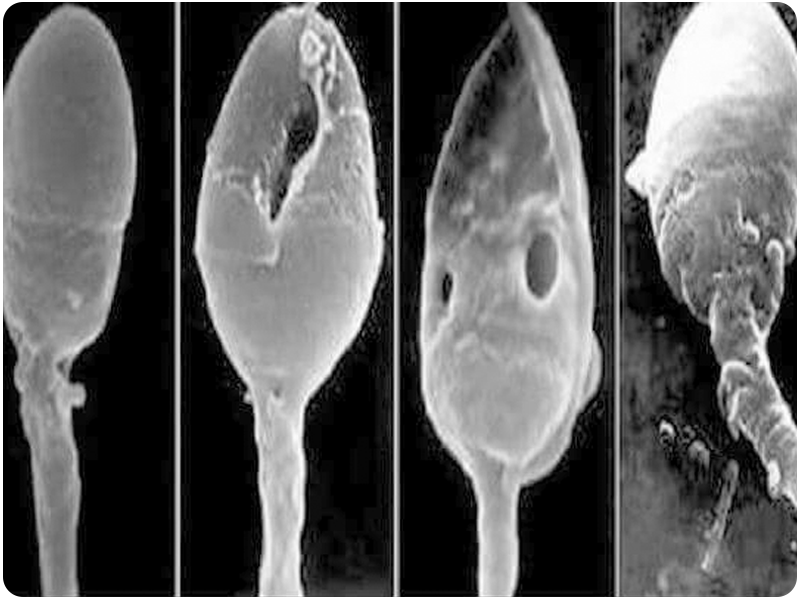

Alteraciones en la Morfología de los Espermatozoides

• Teratozoospermia: La Teratozoospermia o Teratospermia es una alteración del esperma masculino que provoca que más del 96% de los espermatozoides tengan una morfología anómala. Si hay menos de un 4% de espermatozoides con una morfología adecuada se considera que el varón tiene un mal pronóstico y, en este caso, se recomienda recurrir a la Fecundación in Vitro para lograr un embarazo.